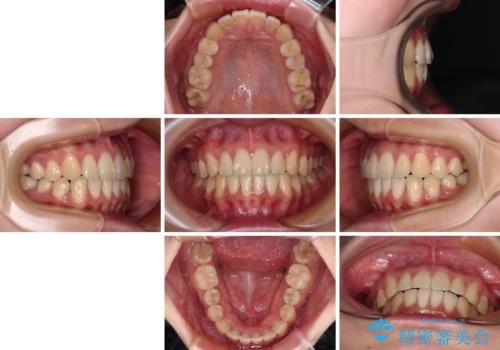

- 前歯の捻れを気にして来院された患者様です。

上顎前歯が捻れて前方に飛び出しており、下顎前歯もそれに沿うようにデコボコとなっていました。

IPR(歯と歯の間を削る処置)によりスペースを獲得して下顎前歯のデコボコを改善し、上顎前歯は下顎前歯と接する位置にまで引っ込めるように設定し、インビザラインにて矯正治療を行うこととしました。

しっかりと装着時間を守ってくださったので、予定通り1年強で治療を終えることができました。